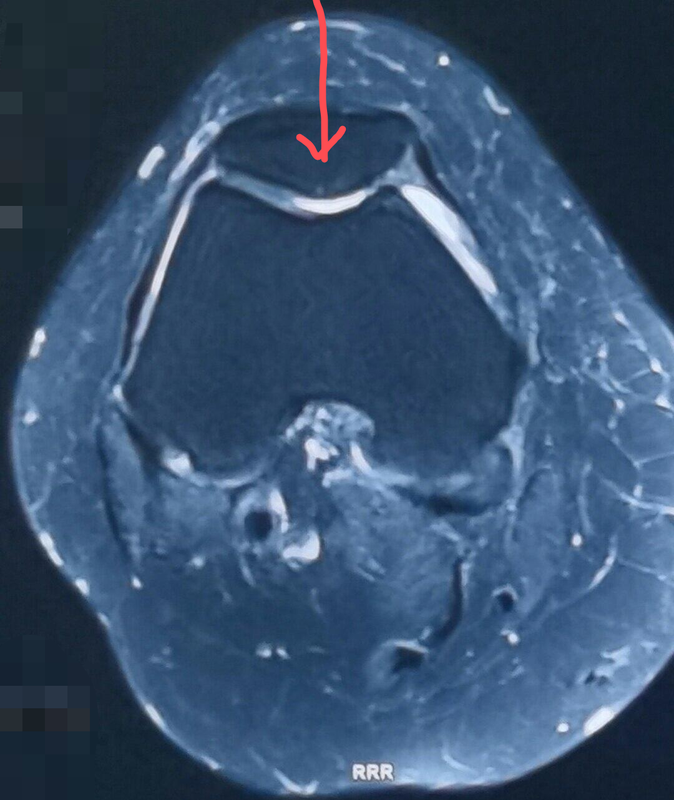

您是否有遇到过这种情况:在您上下楼时、从椅子上或蹲下站起来的时候膝关节前方疼痛?如果是,那您可能就遇到了膝关节最常见的疾病之一:髌骨软骨软化和髌骨关节炎。之所以将这两个疾病放在一起,是因为他们是同一个疾病的不同阶段。髌骨软骨软化 在膝关节运动时,髌骨在股骨滑车的凹槽内滑动,就像小孩子在滑滑梯。髌骨的表面有一层软骨,保证其在滑动时十分顺滑。然而在某些情况下,比如内外侧肌肉力量不均衡,股骨髁发育异常,髌骨发育异常等,髌骨的平衡受到破坏。本来是全关节面受力变成了一侧关节受力,就好像人本来两条腿走路,由于某种原因现在只能一条腿走路。所有的压力都集中在了一侧,压强变大,局部的髌骨就会缺血坏死和脱落。在早期,髌骨仅表现出软骨水肿,轻度损伤、软骨下骨水肿和囊肿等情况,我们称为髌骨软骨软化。随着病情的进一步发展,软骨逐渐碎裂、崩解脱落,软骨下的骨质开始继发性的增生、硬化、骨赘生成,同时导致股骨髁的进一步损伤,病情便转向了髌股关节炎。引自:https://adrianoleonardi.com.br/artigos/tag/cirurgia-da-condromalacia-patelar/髌骨关节炎 髌股关节炎是髌骨和股骨之间关节的退变,主要表现为软骨的不同程度损伤、剥脱,骨赘生成。髌骨软骨软化是髌股关节炎的主要原因之一,当然还有其他的诱因,比如外伤、半月板退变、膝关节力线异常、其他膝关节间室的骨关节炎累及等。此外还要注意,因为膝关节软骨是靠关节内压力波动将关节液挤入软骨内供应营养,因此久站久坐是膝关节各个间室骨关节炎的重要诱因。引自:https://orthoinfo.aaos.org/en/diseases--conditions/patellofemoral-arthritis/非手术治疗 通过合适和正规的治疗,髌骨软骨软化和早期的髌骨关节炎是可以得到缓解和治愈的。前提是你需要找到专业的医生进行合适的诊断,找到病因并对症治疗。非手术治疗可以缓解一大部分的患者:1. 如果体重过大,需要尽快的减重。减重可以显著的恢复膝关节内的各种不适感。2. 如果有结构上的问题,例如股骨髁发育不良、髌骨脱位等情况,需要医生评估,必要时手术治疗。3. 出现症状后需要休息2周,避免负重情况下的屈膝,减少髌骨关节的压力,使软骨得到一定的恢复,但期间需要在床上进行膝关节周围肌肉的锻炼。待症状缓解后开始逐渐恢复负重,加强膝关节周围肌肉及小肌群的锻炼,但避免过度负重。4. 补充多种维生素有利于软骨的营养。尽管有些研究认为硫酸软骨素和氨基葡萄糖对膝关节软骨保护作用甚微,但笔者认为仍然可以尝试。5. 如果症状十分严重,可考虑NSAIDs类抗炎止疼药。其可以缓解一部分的症状,但其可能不利于软骨的修复。6. 关节内注射激素和玻璃酸钠,在一定程度上可以缓解症状,但不宜多次反复进行。一定注意要到正规的医疗机构进行注射,严格的预防感染。 可参考一下康复计划,请在医生指导下进行:手术治疗 在非手术治疗效果不佳的情况下,可以考虑手术治疗。对于无明显力线不良的早中期患者,可以考虑微创关节镜下进行关节内的清理、髌周去神经化和软组织平衡手术。如果软骨损伤较重,不伴明显的关节炎,我们还可以通过骨髓刺激、软骨移植等手术方式进行软骨的修复。对于伴有明显力线异常、髌骨脱位的患者,我们还需要进行力线的矫正手术。最后,对于晚期严重的骨关节炎、合并其他间室的关节炎,我们可以进行关节置换术。